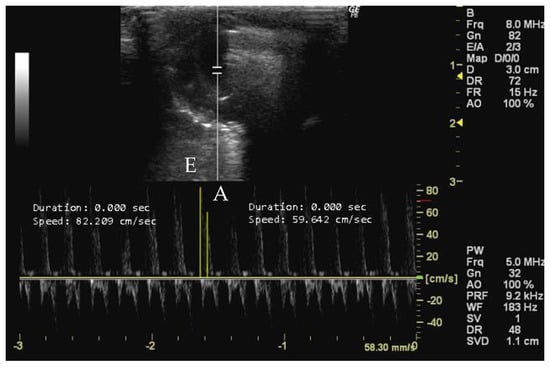

- How to measure E and A peaks

- How to measure LVET